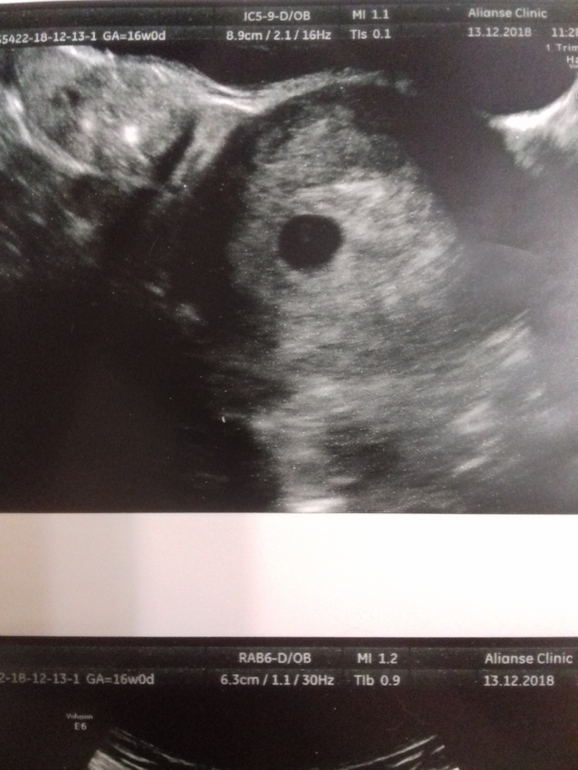

Может у вас поздняя овуляция? Свд еще маленький для эмбриона, но наличие желточного мешочка говорит о том, что скоро должен появиться. Но! бывают исключения( У меня при 11мм не было, при 20мм увидели

У меня в плодном яйце 20 мм не нашли эмбрион. Нашли через неделю в 28 мм. Ждите 12 недель и идите не скрининг, все нормально

В 5н6дн плодное было 14мм. У вас 9мм, значит 5 недель точно есть. Я так понимаю, роды у вас будут в 50 недель 😅😆

У меня в 5 нед ПЯ было всего 6,5 мм, а у вас 9 уже, не понимаю, почему они такой срок поставили. Сходите через недели 1,5, чтобы проверить сердцебиение и эмбриончик. По хгч срок беременности и размер пя ставить неправильно, так как все индивидуально.